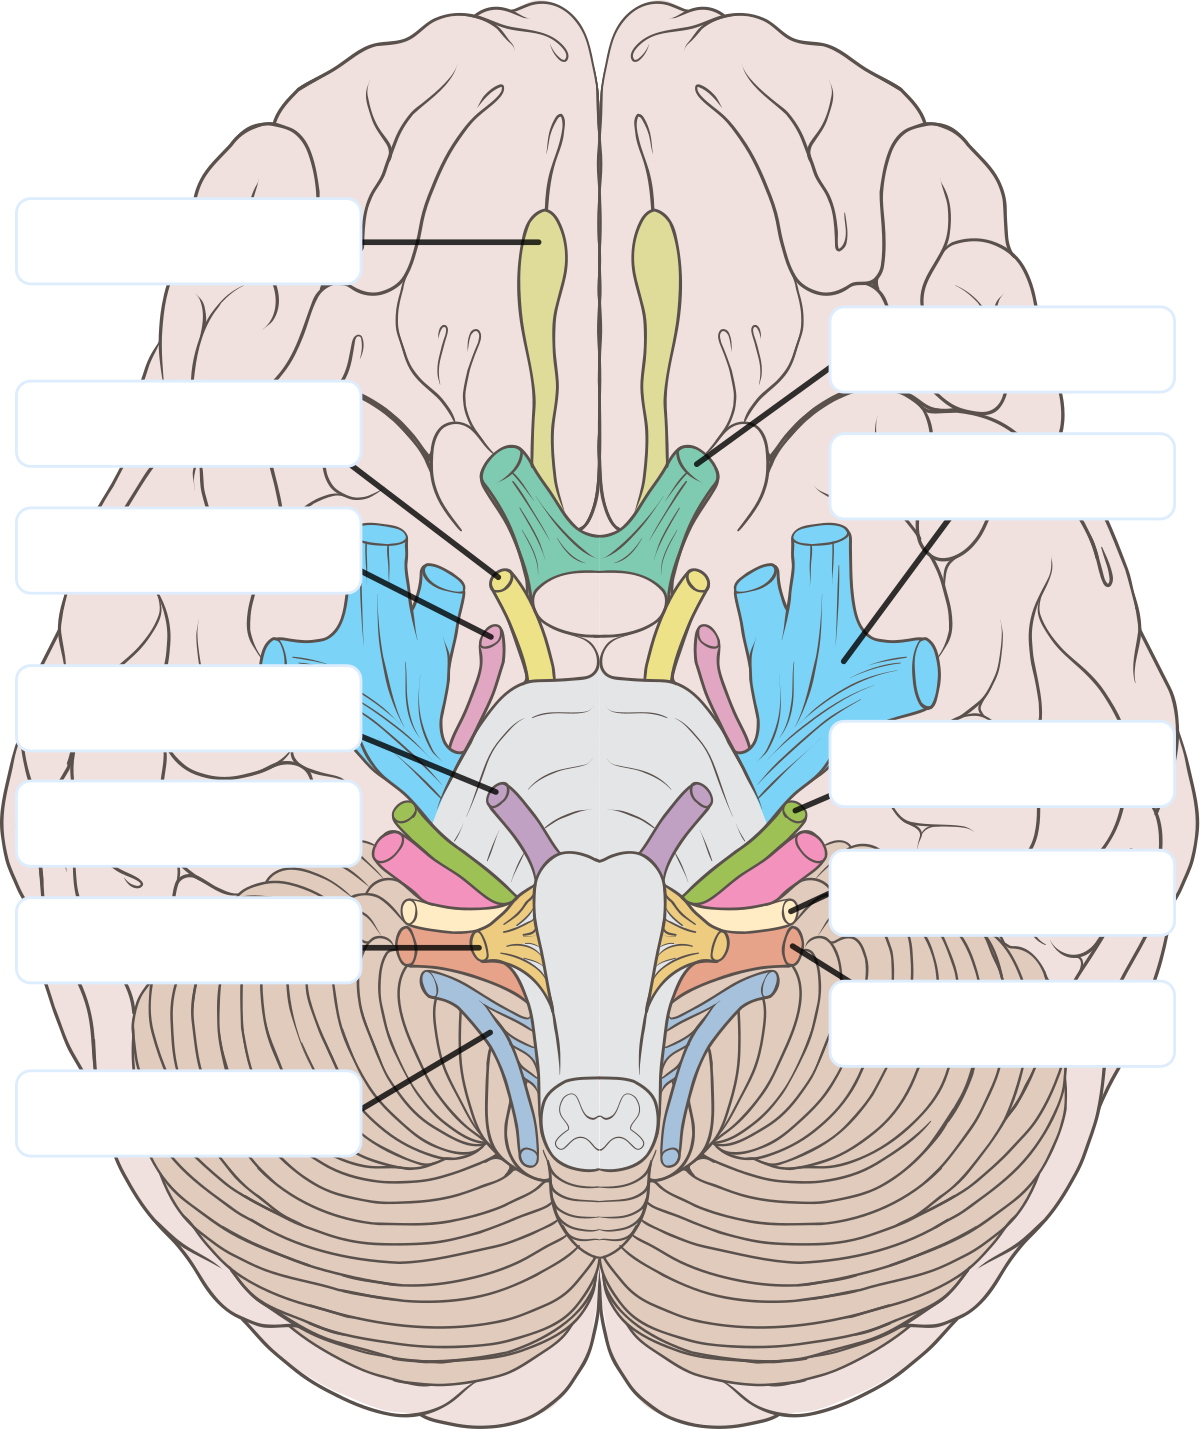

脳神経 Wikipedia